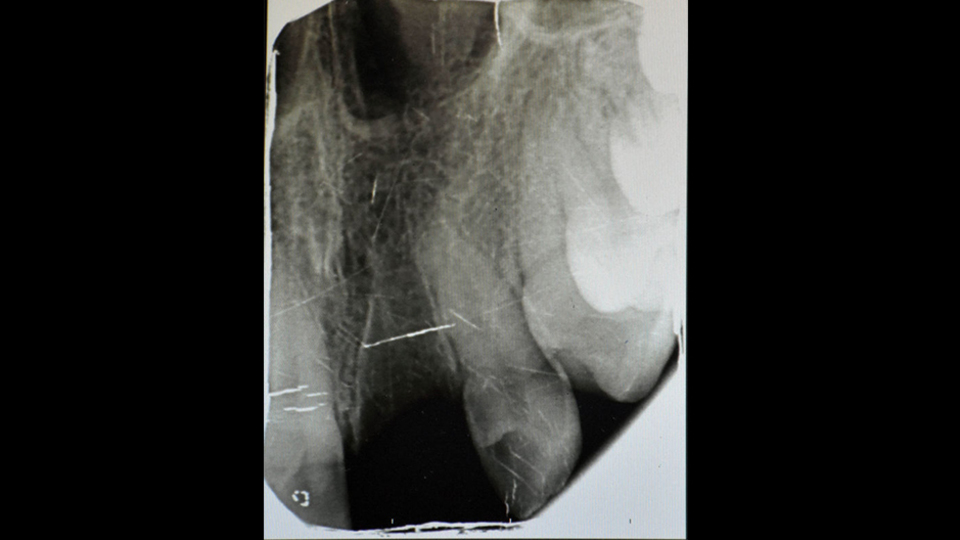

Sivas Ağız ve Diş Sağlığı Hastanesi Diş Hekimi Ersin Kuş ise toplumun dişin yeniden yerine takılabildiği konusunda bilinçsiz olduğunu, dişin yerinden çıkması halinde peçeteye konulmaması, zaman geçirilmeden süt veya ağız içerisinde diş hekimine gidilmesi gerektiğini ifade etti. Ersin Kuş, "Kaza sonucunda yerinden çıkan dişler reimplantasyon yöntemiyle yerine takılabilmektedir. Hastamız da nöbetçi polikliniğimize başvurdu. Hastanın kaza geçirdiğini öğrendim. Muayene yapınca dişlerinin yerinde olmadığını fark ettim. Sonra dişin birinin kendilerinde olduğunu söylediler. O dişi hemen yerine yerleştirdik ve diğer dişi bulmaları için ailesine bilgi verdim. Yarım saat 45 dakika sonra dişi getirdiler. Özellikle süt içerisinde getirmelerini söyledim. Çünkü kuru kalan dişlerin başarı oranı azalmaktadır. Bu gibi durumlarda özellikle süt içerisinde hastanın dişlerini getirmesi süt bulamaz ise ağız içerisinde taşınması önemlidir. Daha sonra dişleri yerine yerleştirdik filmleri aldık. Bir ay boyunca dişi sabitlemek zorundaydık. 4 hafta sonra yapılan kotrolde tedavinin başarılı olduğunu gördüm" ifadelerini kullandı.